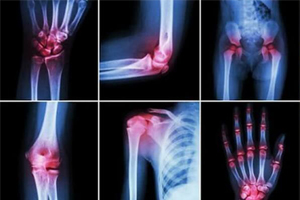

Ревматоїдний артрит (РА) належить до поширених автоімунних захворювань, проблема якого полягає в швидкій інвалідизації особи внаслідок ушкодження синовіальної сумки суглоба. Для сучасної терапії РА характерна патофізіологічна обґрунтованість лікувально-тактичних підходів, що зумовлюють широке застосування хворобо-модифікуючих препаратів синтетичного та біологічного походження (сХМАРП та бХМАРП). Поширення застосування ХМАРП зумовило зниження ризиків інвалідизації пацієнтів та покращення якості життя. Набутий клінічний досвід свідчить про ефективність стратегії «лікування до досягнення мети» на ранніх стадіях РА, яка зумовлює досягнення тривалої ремісії та знижує ризики потенційно небезпечної серцево-судинної коморбідності у пацієнтів з РА [2]. На підставі цього була висунута гіпотеза щодо ефективності застосування бХМАРП, зокрема абатацепту, у пацієнтів з підозрілою серопозитивною артралгією [3]. Механізм дії абатацепту полягає в блокуванні взаємодії між Т-лімфоцитами та антигенпрезентуючими клітинами з подальшою інактивацією патологічних сигнальних шляхів автоімунного запалення. Однак брак результатів ефективності тривалого застосування бХМАРП в клінічній практиці спричинив упередженість стосовно застосування бХМАРП у пацієнтів з РА, та спонукав групу дослідників на чолі з Джованні Гарнотто (G. Garnotto), Університет м. Мальме (Malmö University), Швеція, дослідити ефективність та безпеку застосування абатацепту в клінічних умовах [1]. Результати опубліковані в журналі «Дослідження та лікування артриту» (“Arthritis Research&Therapy”).